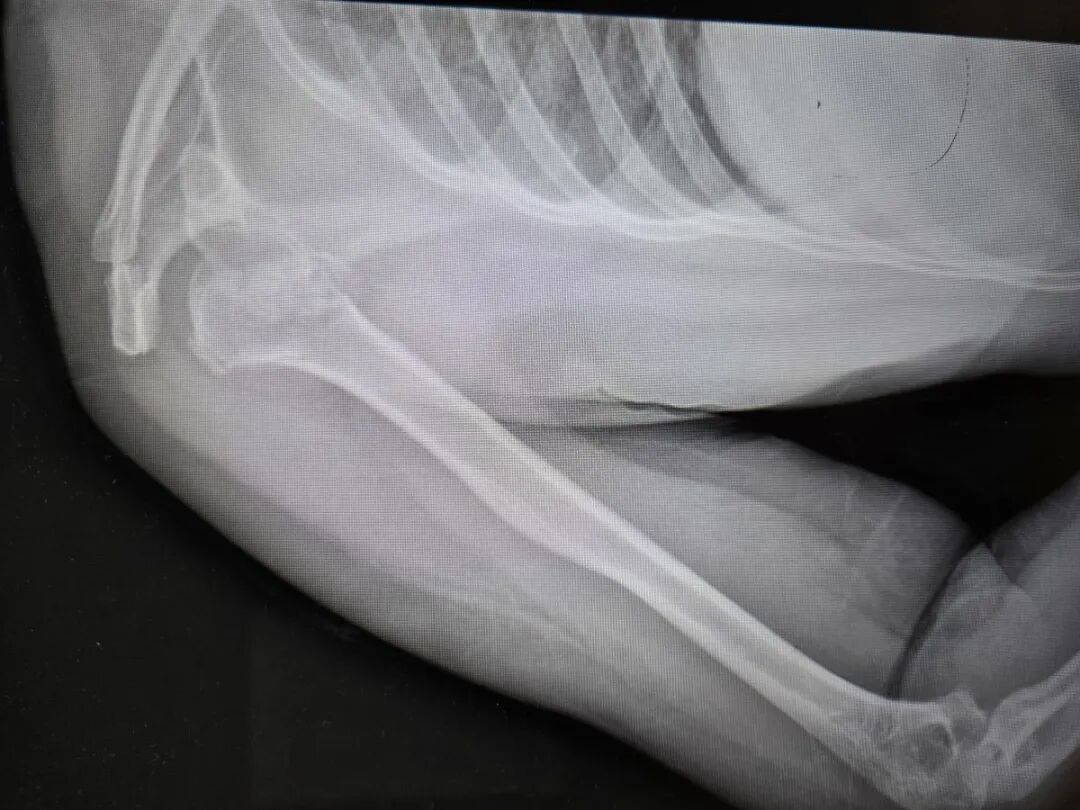

送医后的CT检查结果显示:右肱骨近端四部分粉碎性骨折,且伴有罕见的肱骨头后脱位。她的肩膀碎成了七八块,而且关节位置发生了严重偏移。由于手术难度极大,她被紧急转诊至河南省人民医院。

“肩关节后脱位相当罕见,在所有肩关节脱位中不到4%,而它最常见的诱因就是癫痫发作。”刘涛主任解释道,“前脱位很常见,但后脱位需要非常大的暴力才能造成。”